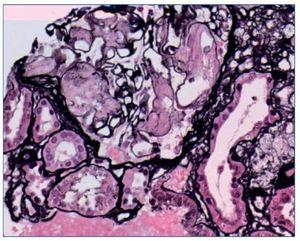

Se plantea la realización de biopsia de grasa subcutánea para descartar depósito amiloide, pero se prioriza la realización de biopsia renal, dado el contexto clínico, y se plantea el diagnóstico diferencial de presunción de nefropatía lúpica membranosa (tipo V) frente a otras nefropatías. Sin embargo, en el estudio anatomopatológico a niveles glomerular y arterial se evidencia depósito de amiloide, débilmente PAS (ácido peryódico de Schiff) positivo, negativo para plata metenamina (fig. 1) y positivo para rojo Congo (fig. 2), con birrefringencia a verde manzana con luz polarizada. El estudio inmunohistoquímico muestra positividad para amiloide A (fig. 3). No se observan imágenes que puedan justificar afectación lúpica renal asociada. En el estudio de microscopia electrónica (fig. 4) destaca la presencia de fibrillas dispuestas de forma aleatoria y con unas medidas comprendidas entre los 9-12 nm de diámetro. No se observan depósitos electrodensos. El estudio de inmunofluorescencia es negativo.

Figura 2. La tinción de rojo Congo muestra birrefringencia verde manzana a niveles glomerular y arterial (20×).